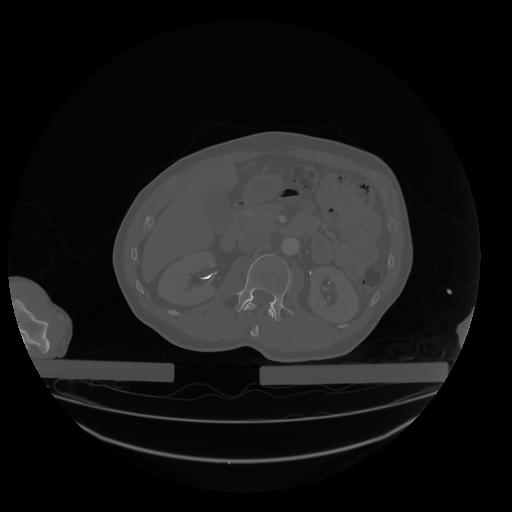

28 CUERPO,CE,Vol,2.0,CUERPO,,